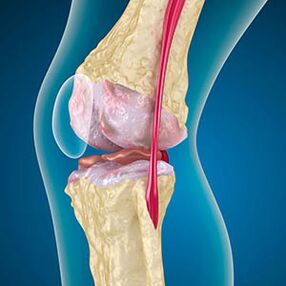

Dans le cas de l'arthrose, le cartilage qui tapisse les bords des os est une abrasion ou un manque. Le tissu endommagé n'est pas une source de douleur car il n'a pas de récepteurs. L'inflammation dans les structures voisines provoque des symptômes caractéristiques.

Le corps continue la régénération des tissus endommagés, mais le cartilage se développe de manière inégale. En conséquence, des irrégularités se forment qui violent d'autres éléments de l'articulation. Le type d'ostéophyte est déclaré cartilage articulaire lisse par compensation. Une autre version montre que la croissance des "éperons"Il est associé à la tentative de stabiliser l'articulation dans le milieu ou latéralement en raison de l'affaiblissement musculaire.

L'image du rayon X montre la présence d'ostéophytes, un changement dans l'espace entre le fémur et les os du tibia, ce qui indique la perte de cartilage dans le genou. Parfois, les rayons X des articulations du genou présentent des signes importants d'usure du cartilage, mais les patients n'ont pas de douleur significative.Au contraire, l'arthrose de la première étape peut perturber la fonction du genouLa cause de la douleur est les muscles hypotoniques.